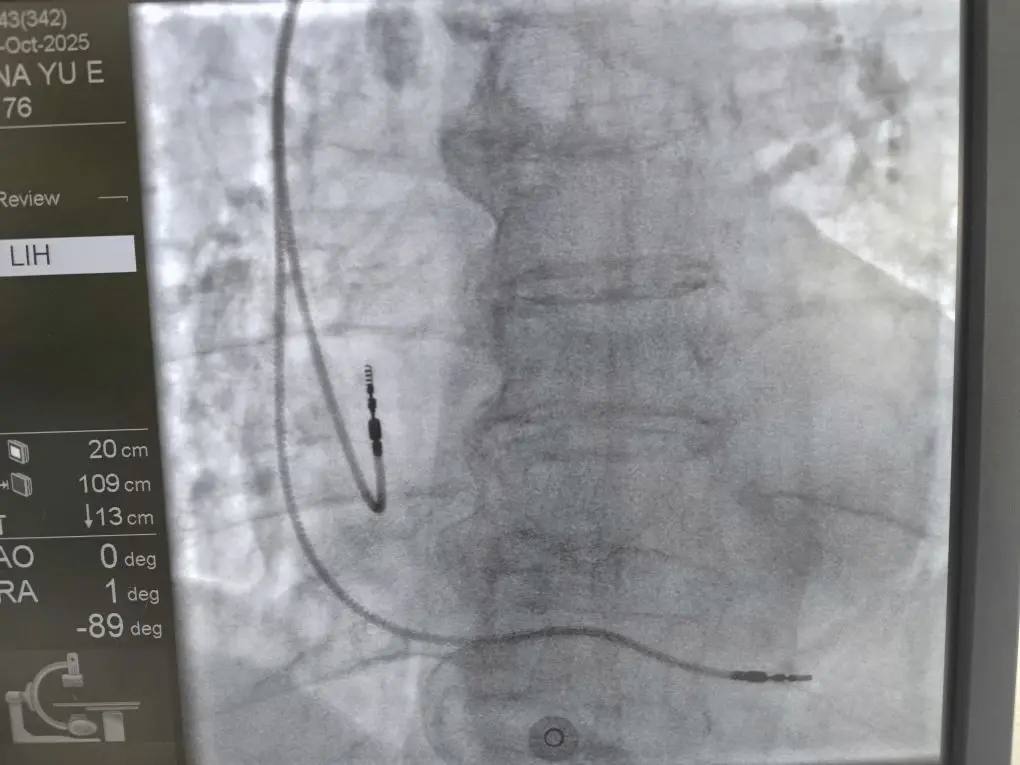

В Республиканской больнице впервые начали проводить операции по установке кардиостимуляторов.

На регулярной основе в Республику будет приезжать сосудистый врач-хирург Илья Стенин с опытом работы в Национальном медицинском исследовательском центре имени академика Мешалкина. Чтобы не только проводить операции, но и обучать наших врачей. В первый день работы прооперированы пять пациентов. Также планируются консультации наших жителей, уже имеющих ЭКС, по вопросам их планового перепрограммирования.

Раньше чтобы попасть на такую операцию, жители ездили в Барнаул или Новосибирск. Теперь такой необходимости нет - процедура доступна в Республике.